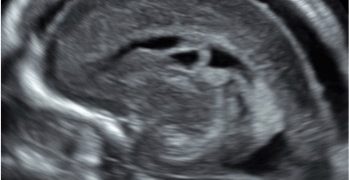

Caso del Mese di Dicembre 2021

Cari soci, finalmente la soluzione del caso del mese di Dicembre! Scarica il File L'attesa è finita: Al seguente link la...